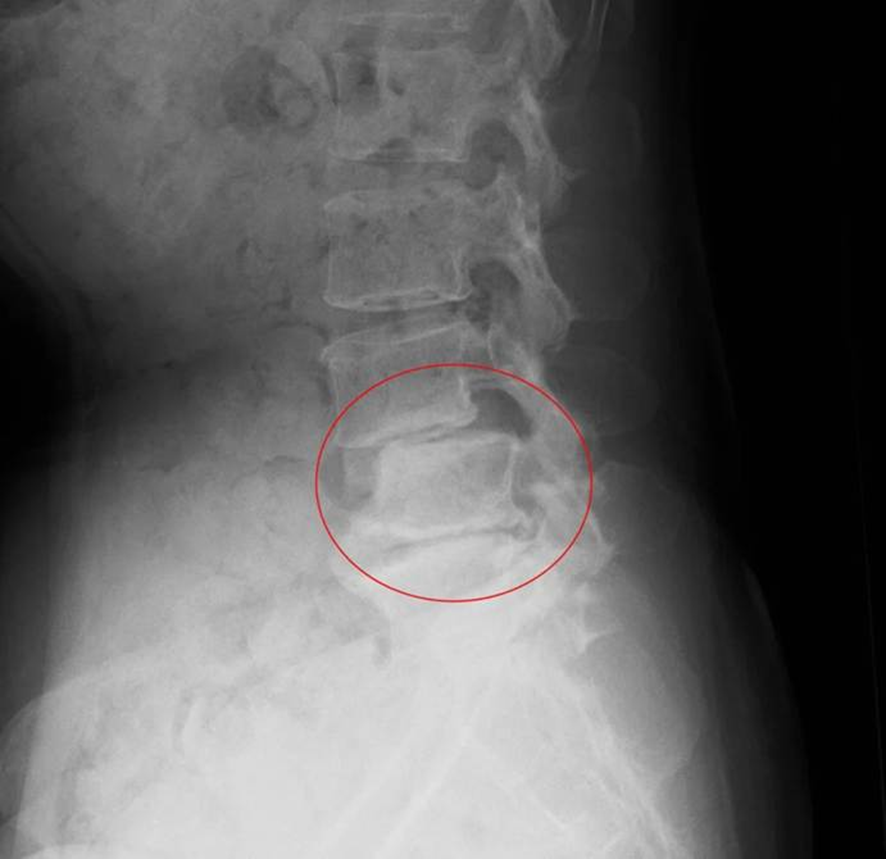

腰椎すべり症とは、腰の部分で椎骨が正常な位置からずれた状態をいいます。

すべり症は骨が前方にすべる「前方すべり」と後方にすべる「後方すべり」があります。